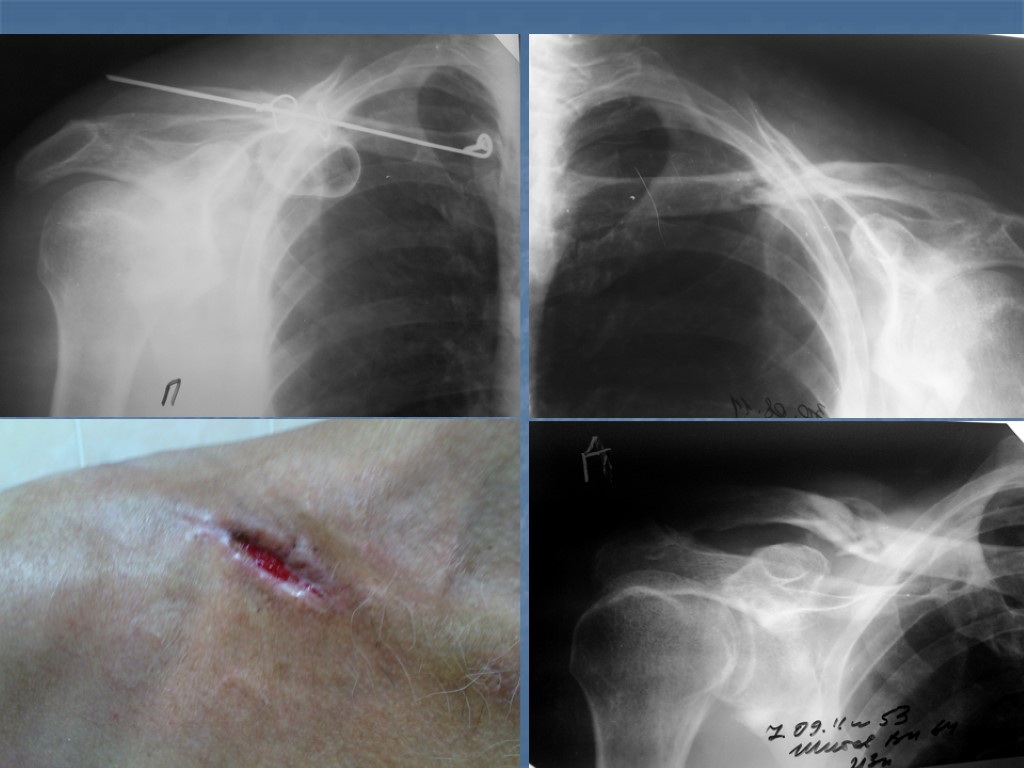

Спица В Ключице Фото